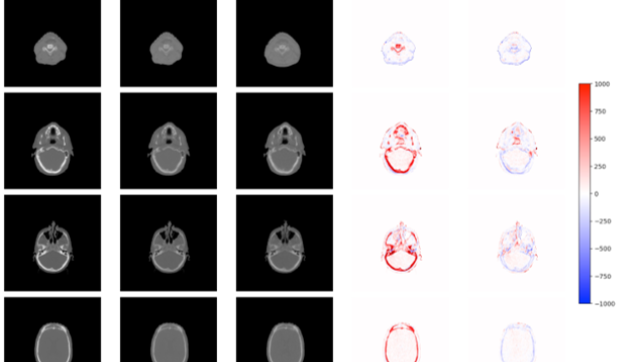

Training Multimodal Foundation Models on Clinical CT Volumes, Radiology Notes, and Structured Data